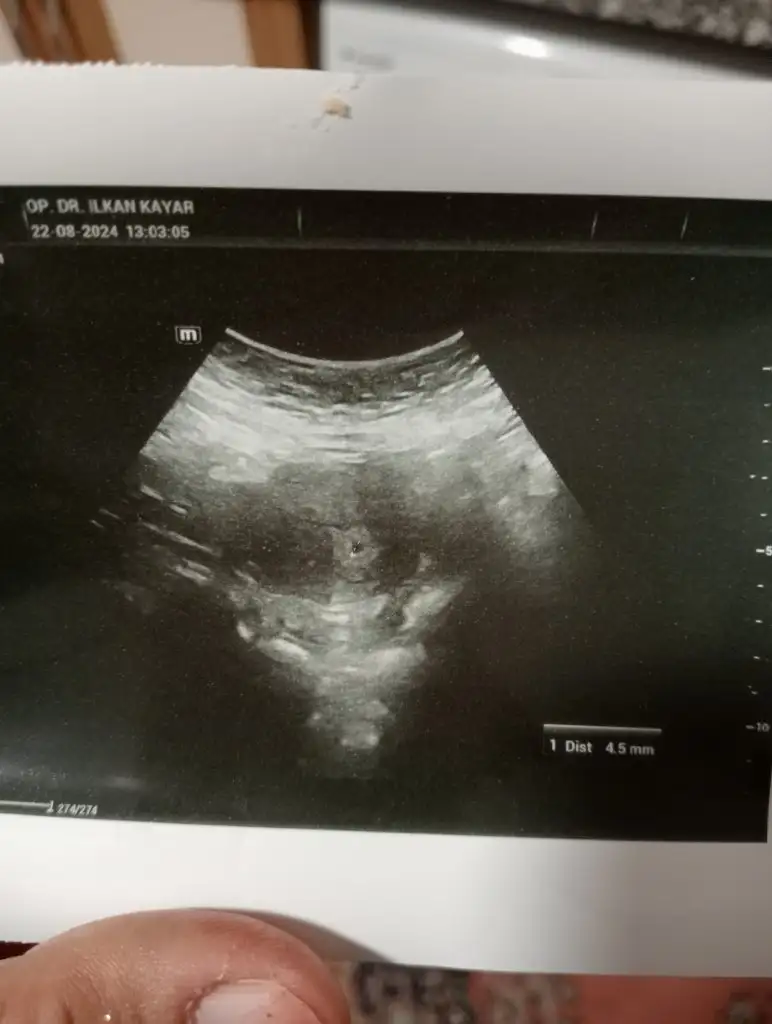

Canım kızlar şükür bugün doktora gittim ve kese gözüktü 🥹 bugün tam 5+0 ilk defa karnımdan gözüktü kese diğer hamileliklerimde hep vajinal muayene olurdum biraz da kilom var diye. Çok karmaşık duygular içindeyim bu bebiş Rabbimin bana nasip ettiği bir mucize🤍 Rabbim tüm bekleyenlere bu güzel haberi ve mutluluğu nasip etsin inşallah 🌸

Eki Görüntüle 3469590